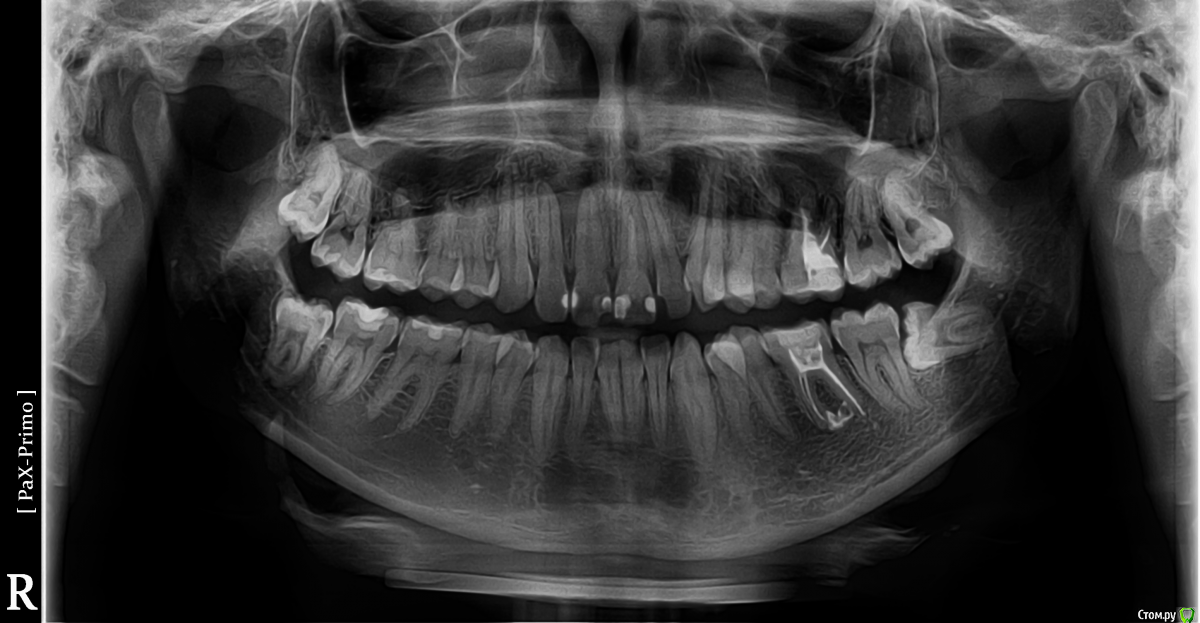

Chelsea Опубликовано 23 апреля, 2018 Поделиться Опубликовано 23 апреля, 2018 Добрый день! Мне предстоит удаление двух нижних зубов мудрости, однако недавно узнал об опасности задеть нижнечелюстной нерв и об ужасных последствиях этого. Прошу посмотреть рентген и хотя бы приблизительно определить опасность моей ситуации..Снимок прилагается.Большое спасибо! Ссылка на комментарий

Irouil Опубликовано 23 апреля, 2018 Поделиться Опубликовано 23 апреля, 2018 Маловероятно справа, не представляет опасности для нерва слева. 2 Ссылка на комментарий

Chelsea Опубликовано 25 апреля, 2018 Автор Поделиться Опубликовано 25 апреля, 2018 Извините что беспокою. Сегодня узнал об опасности перфорации гайморовой пазухи при удалении верхних зубов мудрости. Можно ли по моему рентгену определить на сколько близко гайморовая пазуха расположена к корням зубов мудрости? Какая вероятность перфорации?Большое спасибо!! Ссылка на комментарий

Irouil Опубликовано 25 апреля, 2018 Поделиться Опубликовано 25 апреля, 2018 Если удалять аккуратно, то практически нулевая справа, очень маловероятно слева. 1 Ссылка на комментарий